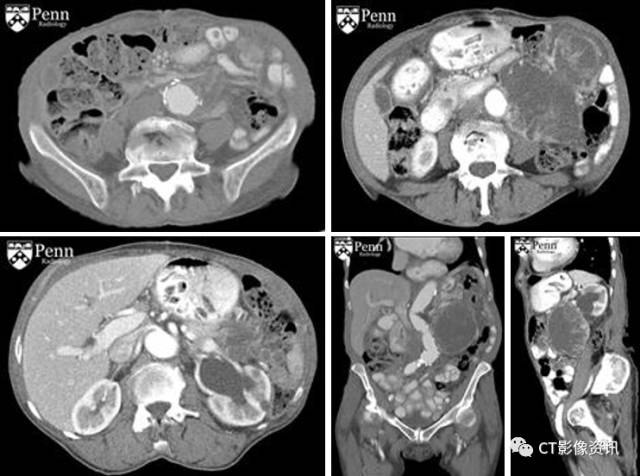

形象学特点: 主要特点:腹膜后巨大肿块,确诊时通常10cm或大于10cm;影像学缺乏特异性,随肿瘤成分的不同影像学表现有较大的差,可以有较大的囊性坏死成分,脂肪和钙化少见。 CT:可见巨大腹膜后肿块,伴囊性和(或)坏死密度;增强扫描呈不均匀强化。 MRI:T1-加权:等到低信号;T2-加权:由于囊性或坏死成分呈等到高信号;增强扫描:不均匀强化。